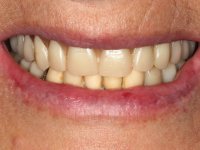

Patient was not able to stabilize or retain the inferior acrylic partial denture.

Female patient, 57 years-old, non-smoker, with a full denture in the maxilla and a removable partial denture in the mandible. Teeth 43-41-41-31-32 were indicated for extraction. Posterior sectors of the mandible presented significant bone resorption.